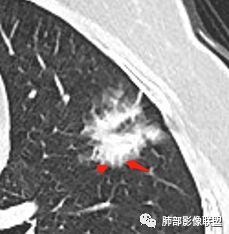

2.病灶的胸膜牵拉线与其间病灶胸膜侧的磨玻璃边构成朝向胸壁的“月牙铲”结构,这种影像学表现某种程度上反映出病理学特征——病灶收缩+小叶间隔阻挡。

月牙铲

在影像上观察到肿块或磨玻璃结节一侧的内凹,像个月牙铲形态,病理是肿瘤生长受到小叶间隔阻挡并受肿瘤内部的收缩力形成,王兆宇老师称之为“月牙铲”!对诊断肺腺癌较有特异性。